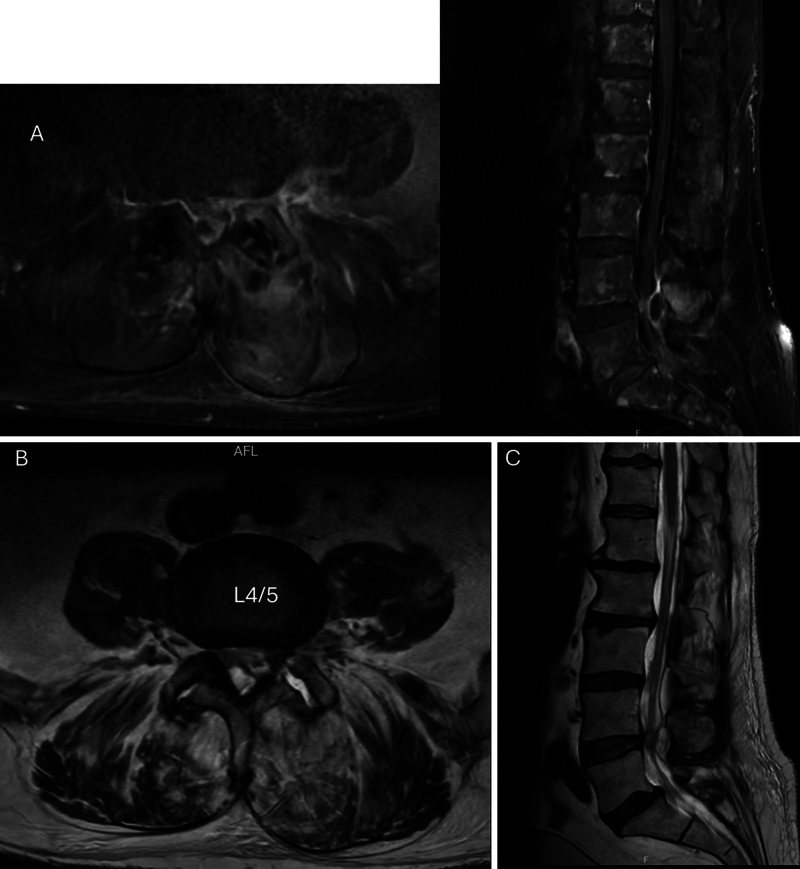

Observations: A 70-year-old male with a past medical history of immunoglobulin A lambda smoldering myeloma degenerative lumbar disease who presented with low back and radicular lower extremity pain was found to have a left L4-5 septic facet cyst with extension to the epidural space. Intraoperative cultures were positive for Nocardia species. Staging workup revealed progression to high-risk-profile multiple myeloma.